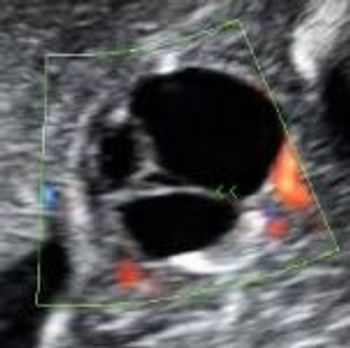

QUIZ: These images are of the fetal heart reveal an abnormality. Can you identify it?